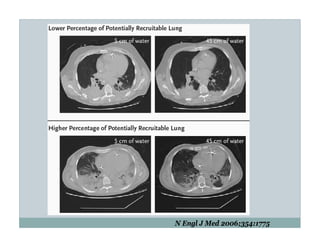

This document discusses the use of positive end-expiratory pressure (PEEP) in patients receiving mechanical ventilation. It describes a 19 year old female patient with immunosuppression and CMV pneumonia who requires intubation and mechanical ventilation. The goal of using PEEP in this patient is to decrease the risk of ventilator-induced lung injury while also aiming to increase oxygen levels and decrease the need for high oxygen supplementation. The document then reviews evidence and controversies around optimizing PEEP levels to reduce lung injury and improve outcomes in acute lung injury and acute respiratory distress syndrome patients.